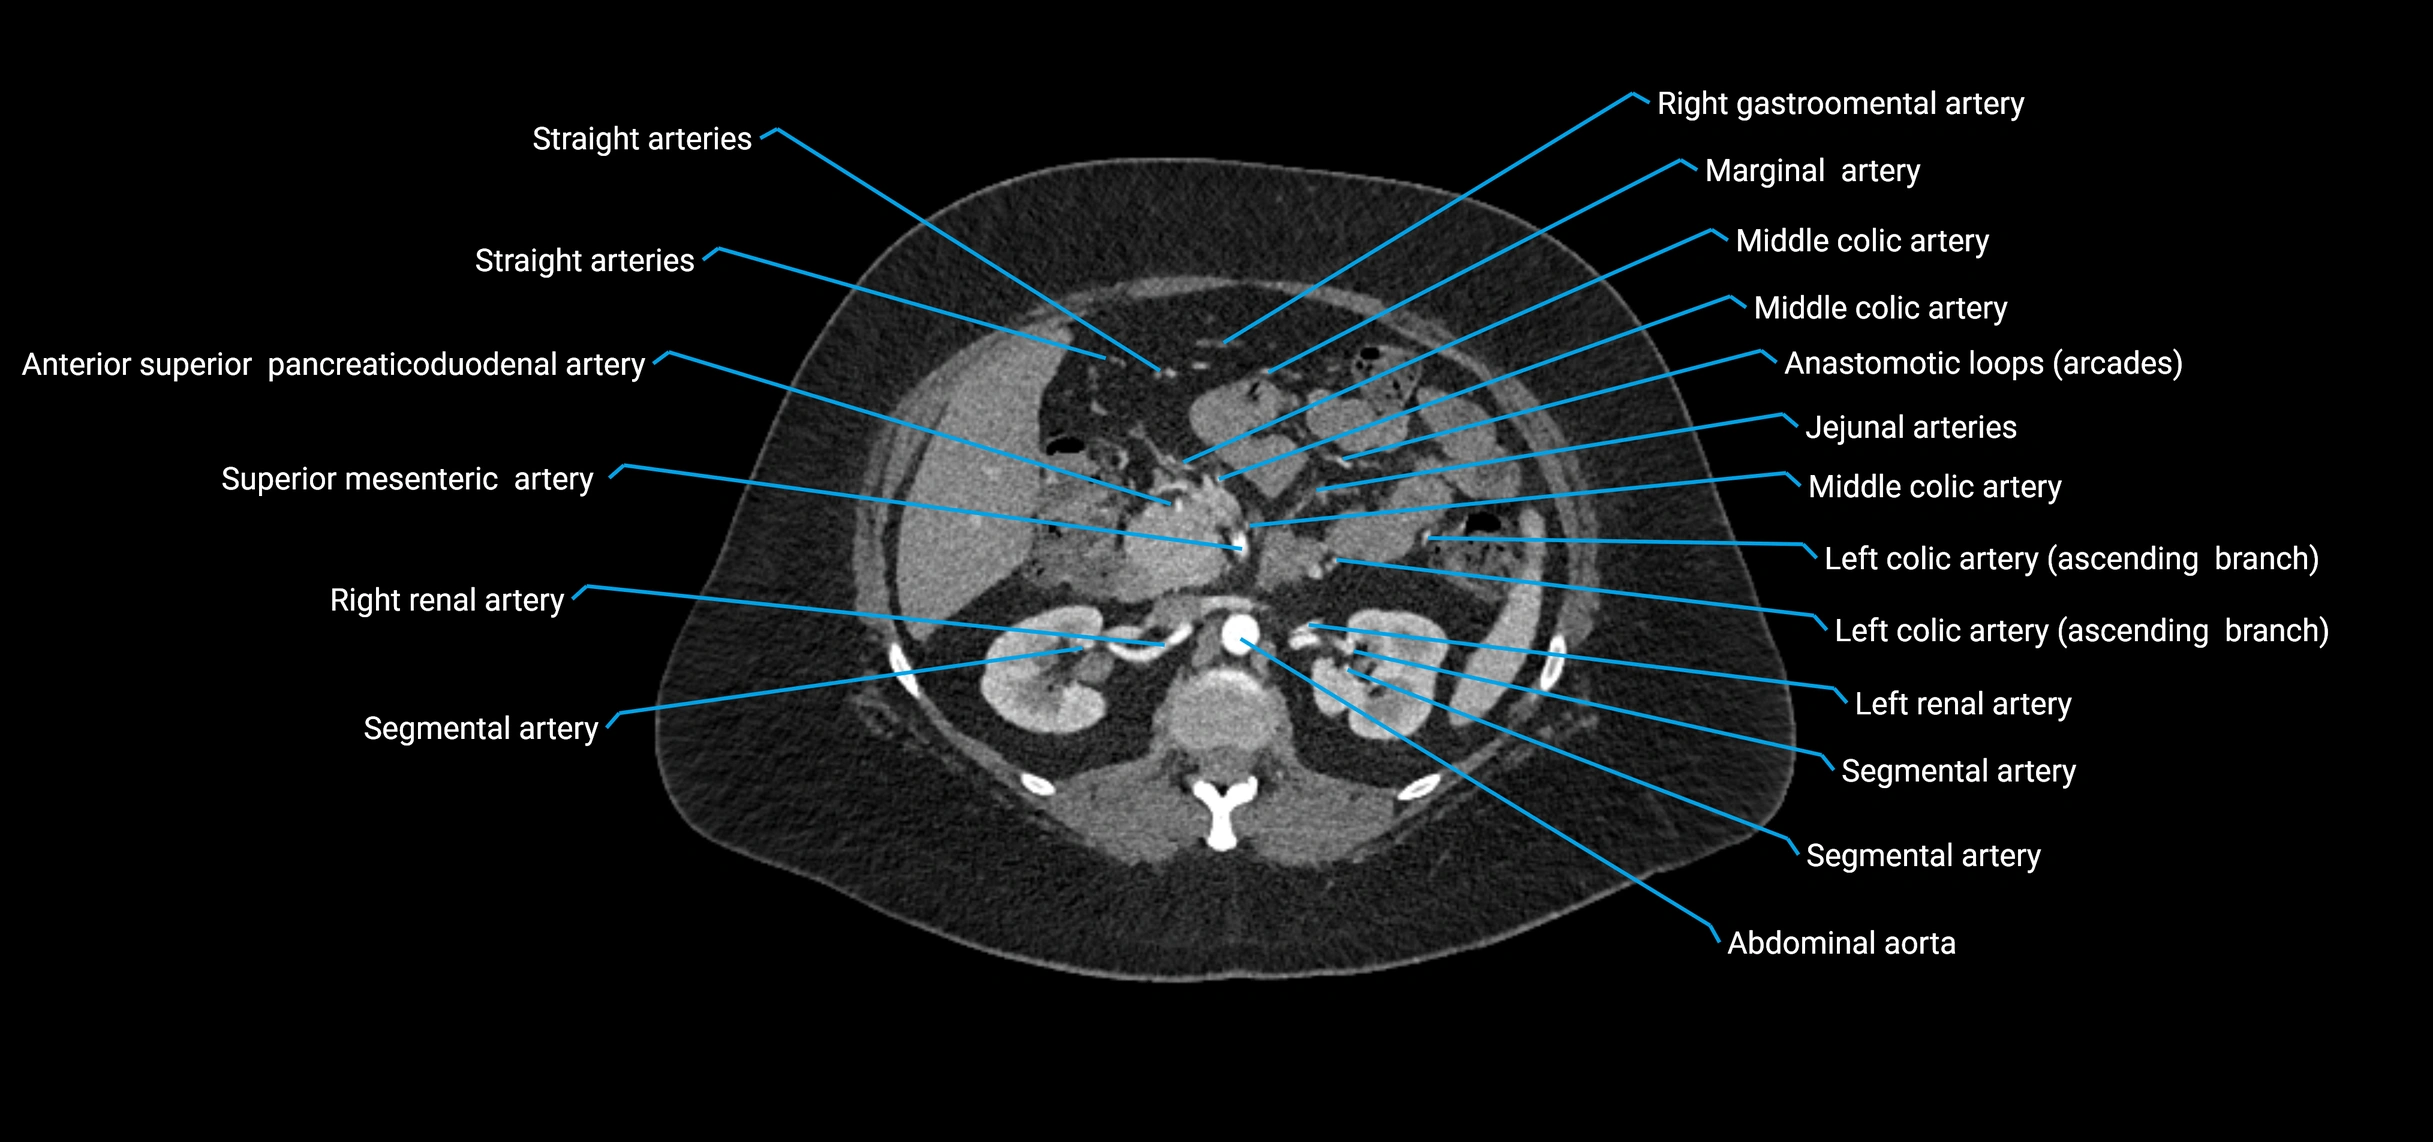

Branches

• Unpaired visceral branches: celiac trunk, superior mesenteric artery (SMA), inferior mesenteric artery (IMA)

• Paired visceral branches: middle suprarenal arteries, renal arteries, gonadal arteries (testicular or ovarian)

CT Appearance

Non-contrast CT:

• Appears as a tubular soft tissue structure anterior to vertebral bodies

• Calcified atherosclerotic plaques appear as hyperdense foci along the wall

• Useful for screening abdominal aortic aneurysm (AAA) size and mural calcification

Contrast-enhanced CT (CTA):

• Gold standard for abdominal aortic imaging

• Provides excellent detail of lumen, wall, aneurysm, thrombus, and branch vessels

• Multiplanar and 3D reconstructions help in aneurysm measurement, stent graft planning, and dissection evaluation

• Detects acute rupture, traumatic injury, or occlusion with high sensitivity

CT images

image